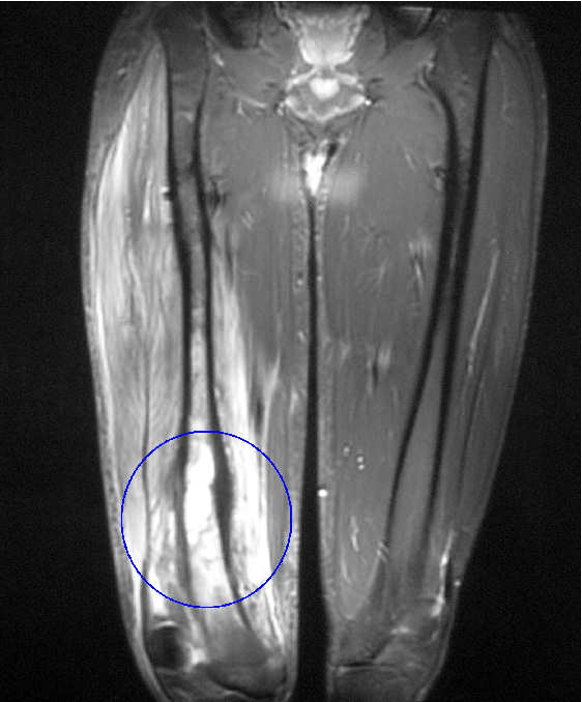

TAC y RMN:

Excelente resolución.

Incluso antes de las radiografías: RMN detecta cambios en 3 a 5 días de inicio de la infección.

TAC es mejor para hueso y RMN mejor para tejidos blandos.

No sirve para seguimiento.

Edema en médula ósea:

Hipointensidad en T1 e hiperintensidad en T2, con reforzamiento tardío con el contraste.

Abscesos con reforzamiento con contraste.